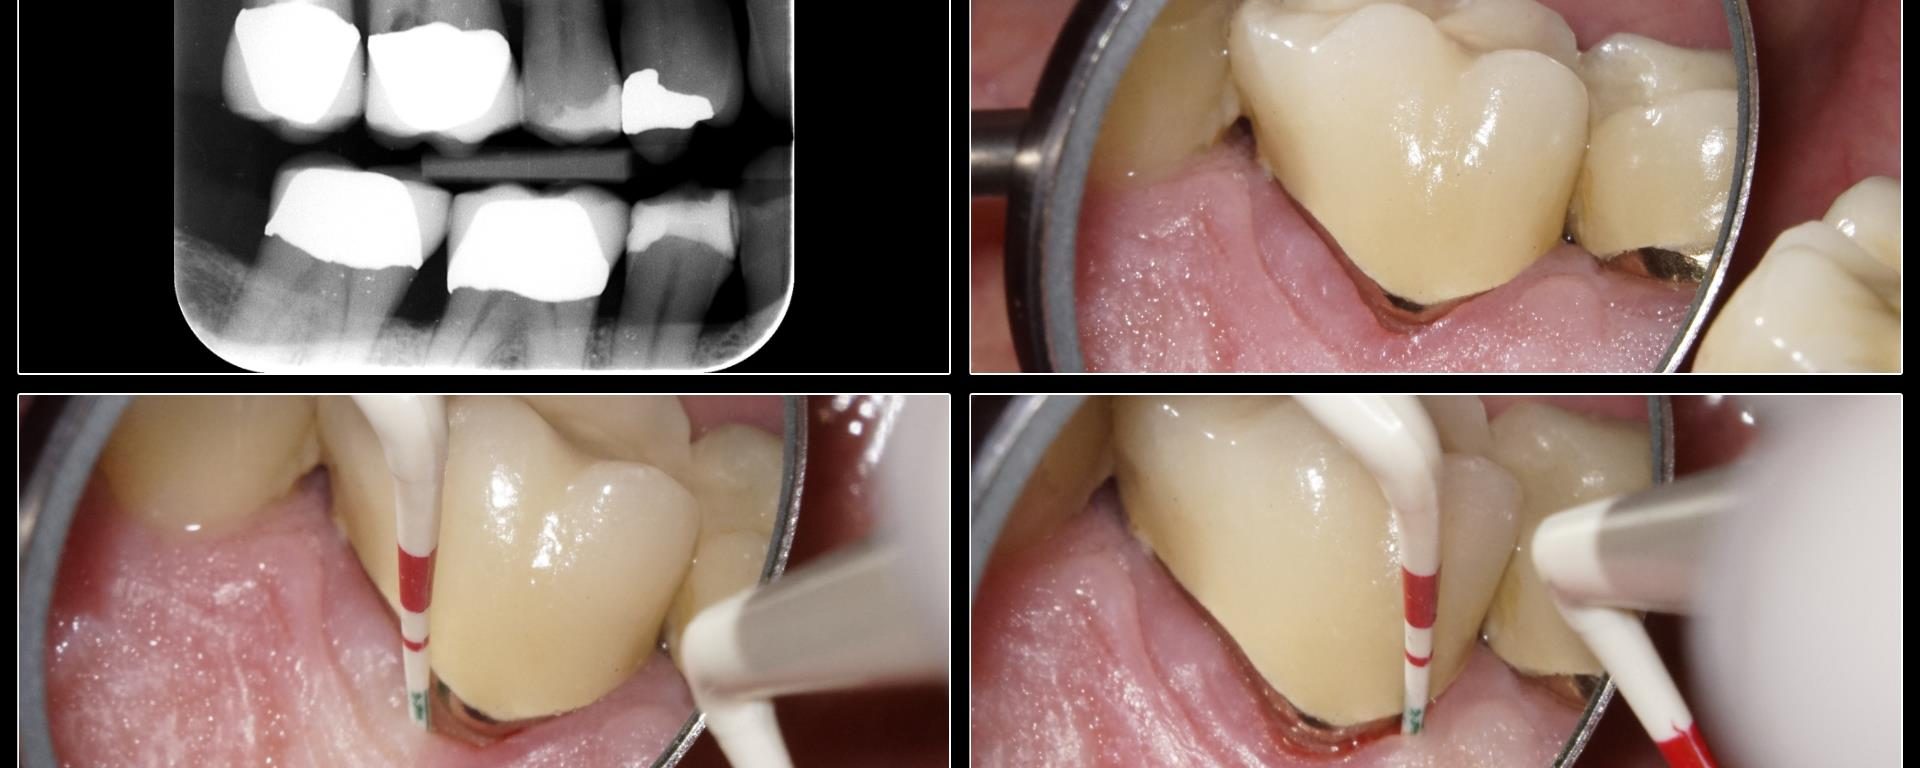

https://schwed.com/product/gonon-post-remover-system/ https://www.endoruddle.com/PRSd Don't use the trephines.   Taper the post in the microscope with a round-ended, tapered diamond like the 856-016 in the CK diamond access kit. http://www.clinicalresearchdental.com/products.php?product=Clark-Khademi-Diamond-Endodontic-Kit%2A https://www.sswhitedental.com/index.php/product-kit-instruments Use the 856-016, 859-010 needle diamond to cut away all the coronal restorative that would interfere with rotation of the post. Taper the post with the diamond.  […]